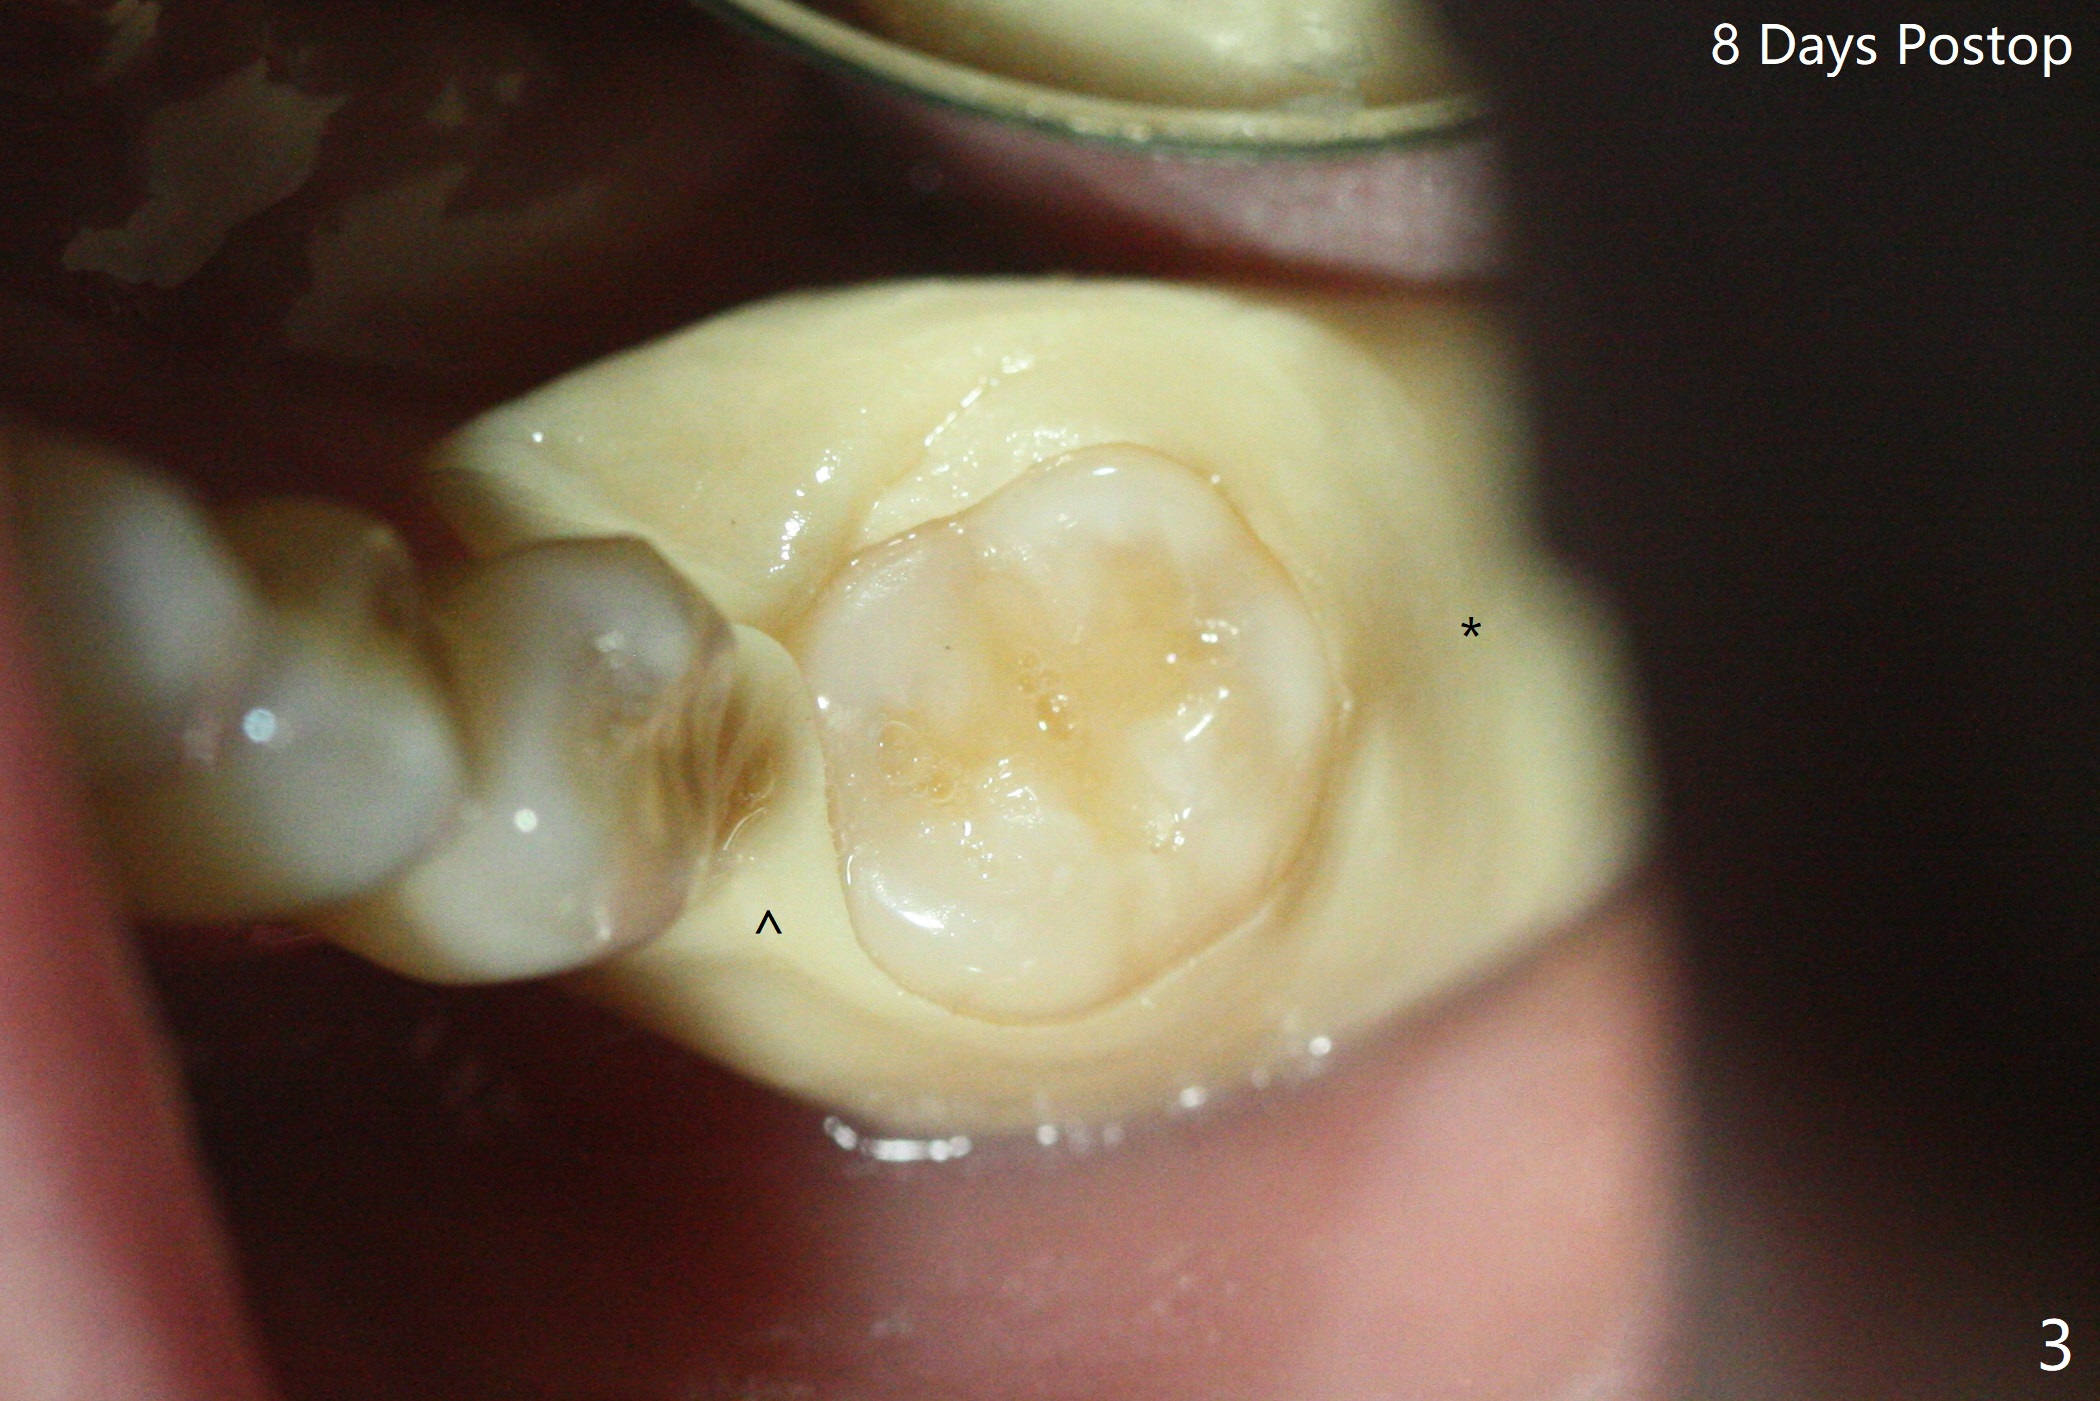

39岁女渴望有一个正常19号牙(图一),第一步,17号牙拔除,粘性骨粉植骨(图二:*),PRF覆盖,树脂敷料。后者术后八天由于倒凹(图三:^),稳定,下面(*)骨粉谅必安居乐业。术后一两个月(伤口愈合,18号牙牙冠远中面充分暴露)后,准备口扫做局部矫正(Clear Aligner),竖直18号牙,植骨有利于18号牙进入17号牙牙槽窝。然后再口扫制作19号牙种植导板。